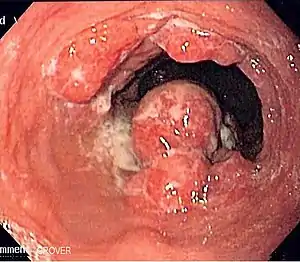

Although an occlusive tumor may be suspected on a barium swallow or barium meal, the diagnosis is best made with an examination using an endoscope. This involves the passing of a flexible tube with a light and camera down the esophagus and examining the wall, and is called an esophagogastroduodenoscopy. Biopsies taken of suspicious lesions are then examined histologically for signs of malignancy.

Endoscopic image of Barrett esophagus – a frequent precursor of esophageal adenocarcinoma

Esophageal cancers are typically carcinomas that arise from the epithelium, or surface lining, of the esophagus. Most esophageal cancers fall into one of two classes: esophageal squamous-cell carcinomas (ESCC), which are similar to head and neck cancer in their appearance and association with tobacco and alcohol consumption—and esophageal adenocarcinomas (EAC), which are often associated with a history of GERD and Barrett's esophagus. A rule of thumb is that a cancer in the upper two-thirds is likely to be ESCC and one in the lower one-third EAC.